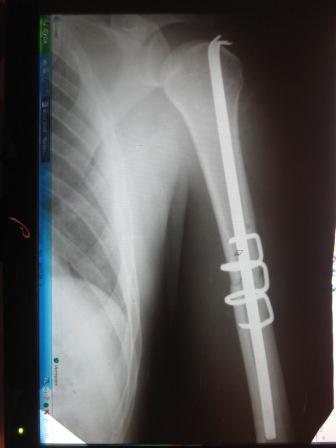

[Ortho] Перелом плеча

Имя     : ФАХРАТОВ (3).JPG